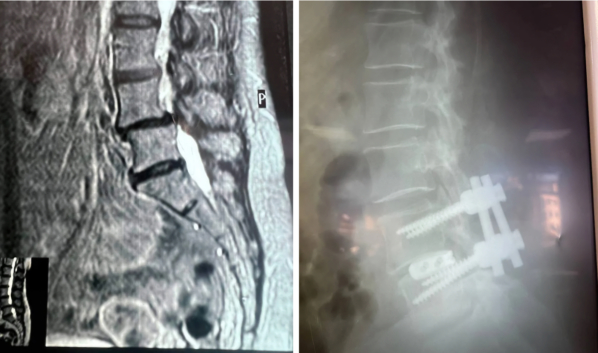

Обследование показало сразу несколько проблем, включая поражение межпозвоночных дисков и комбинированный стеноз позвоночного канала на уровне четвертого и пятого поясничных позвонков.

Во время хирургического вмешательства врачи устранили сдавливание с двух сторон, удалили грыжу и заменили поврежденные диски имплантами. Используя микрохирургическую технику, оптический прибор и специальный инструментарий, специалисты ликвидировали компрессию дурального мешка и сегментарных нервов. Кроме того, медики исправили смещение позвонка. Для стабилизации позвоночника установили конструкцию из четырех титановых винтов и двух балок.